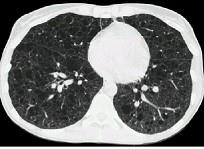

问题 女,33岁,气短伴咳嗽2周,CT检查如图,最可能的诊断为 ( )

选项 A.肺间质纤维化 B.肺淋巴管肌瘤病 C.慢性支气管炎并感染 D.硅沉着病 E.肺囊肿并感染

答案 B